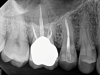

(1.) Preoperative CBCT scan showing Class 2 ECR defects on teeth Nos. 3 and 4 that were surgically accessible.

Figure 1